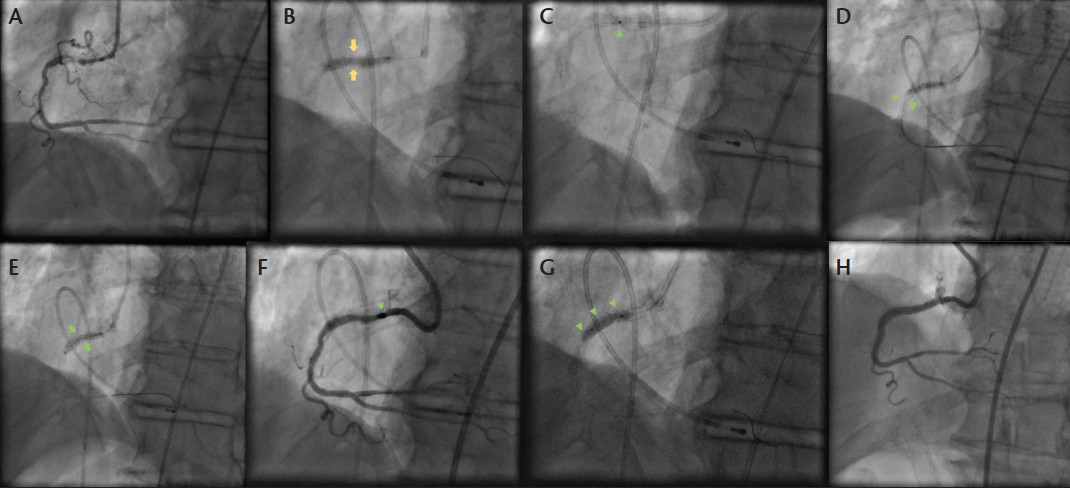

Figure 2. Clinical case representing the challenges of balloon undilatable CTO treatment requiring multiple aggressive methods to achieve successful recanalization. Proximal right coronary artery CTO within a previously implanted stent (A). The CTO was successfully crossed with wire escalation, but the lesion remained underexpanded (yellow arrows) despite balloon multiple high-pressure balloon inflations (diameters of 2.5/3/3.5 mm) (B). Laser coronary atherectomy (green arrowhead) with contrast injection also failed to properly expand the lesion (C). The buddy wire technique was also ineffective (green arrowheads) (D). Two simultaneous balloon inflations (green arrows) also failed to expand the lesion (E). Multiple runs of in-stent rotablation were performed with upsizing the burr size up to 2.15 mm (green arrowhead) (F). Finally, use of an AngioSculpt scoring balloon facilitated lesion dilation and stenting of the lesion (G). Final angiographic result (H).